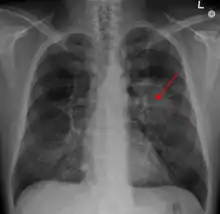

X-ray with an arrow pointing to a hazy circular mass in the chest

A chest X-ray showing a tumor in the lung (marked by arrow)

A person suspected of having lung cancer will have imaging tests done to evaluate the presence, extent, and location of tumors. First, many primary care providers perform a chest X-ray to look for a mass inside the lung.[8] The X-ray may reveal an obvious mass, the widening of the mediastinum (suggestive of spread to lymph nodes there), atelectasis (lung collapse), consolidation (pneumonia), or pleural effusion;[9] however, some lung tumors are not visible by X-ray.[5] Next, many undergo computed tomography (CT) scanning, which can reveal the sizes and locations of tumors.[8][10]